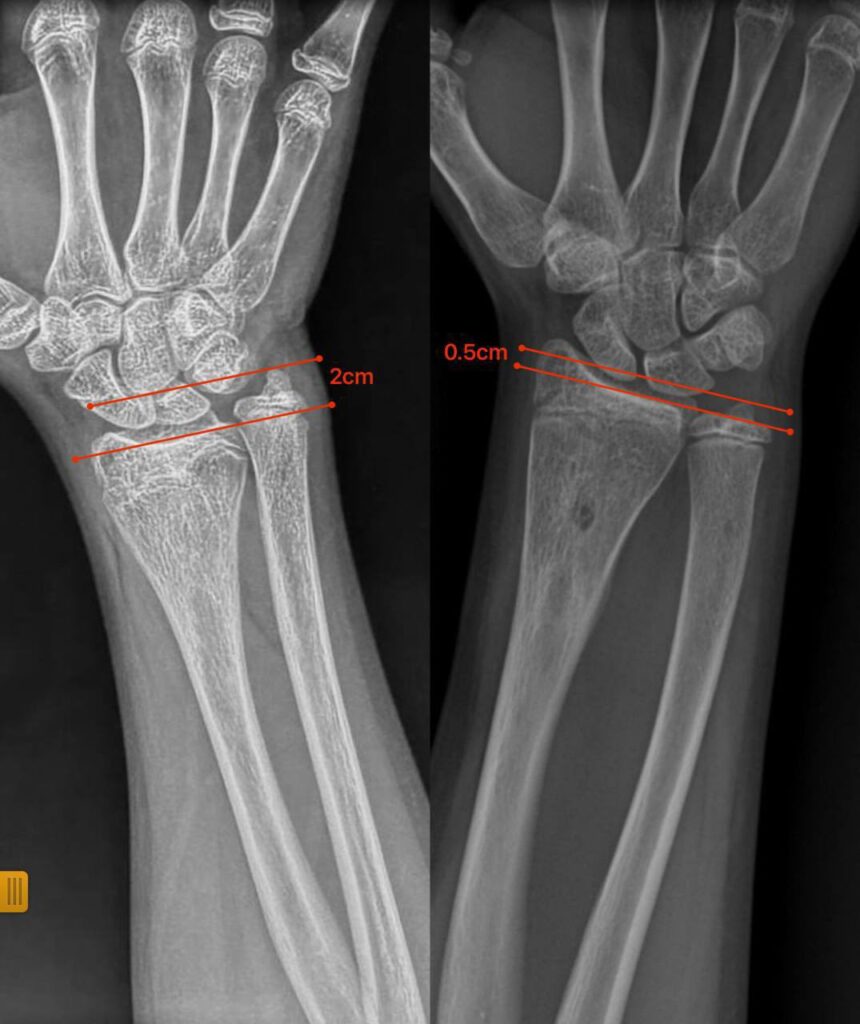

Нещодавно до відділення звернулися батьки 12-річної дівчинки з іншої області з післятравматичною деформацією кісток передпліччя. Лікарі виявили, що ріст кістки порушився через утворення кісткового мостика який заважав росту кістки та деформував її.

Під час операції спеціалісти видалили кістковий місток під контролем ендоскопа. Такий малотравматичний підхід дозволив відновити природний ріст кістки без складних остеотомій чи встановлення металоконструкцій.

Через сім місяців передпліччя дівчинки повністю відновило форму, ріст кістки нормалізувався, а рухливість кінцівки збережена.

Цей випадок демонструє, що не всі деформації потребують складних оперативних методик: іноді достатньо усунути першопричину порушення росту, щоб кістка розвивалася природним шляхом.